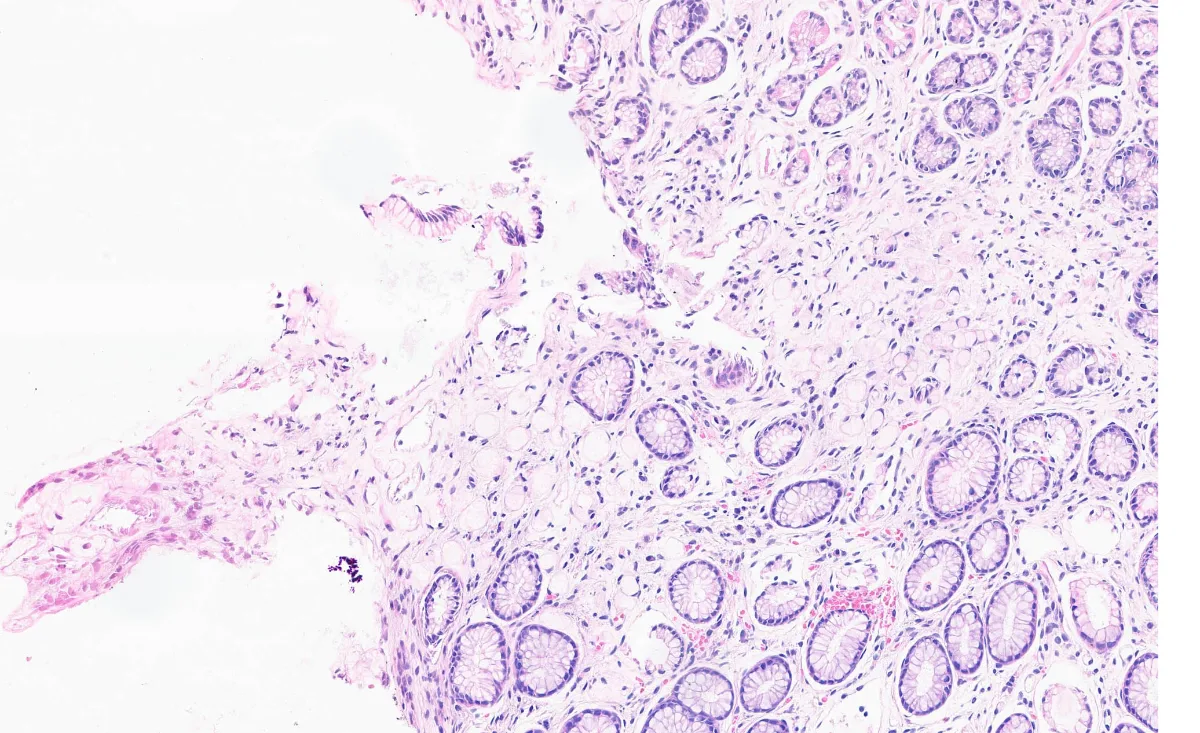

2. BIOPSIA HE X400

5. GASTRECTOMÍA HE X400